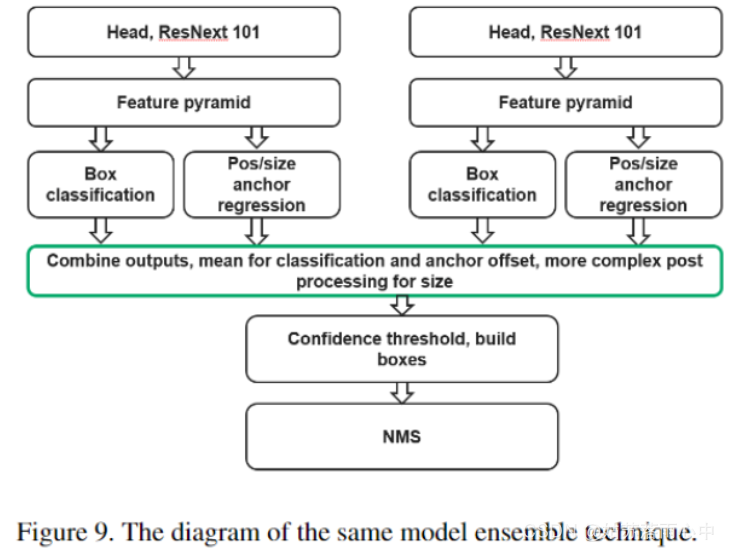

可以使用4倍的输出和/或多个检查点的预测来模拟此过程。使用20个百分位数代替锚点大小的平均输出,然后根据单个模型的80个百分位数和20个百分位数之间的差异按比例减少更多(以1.6的比例作为超参数进行了优化)。

检测模型的结果可能在各个epoch之间发生显着变化,并且很大程度上取决于阈值。在应用NMS算法和优化阈值之前,将相同模型的4折交叉验证的输出合并。